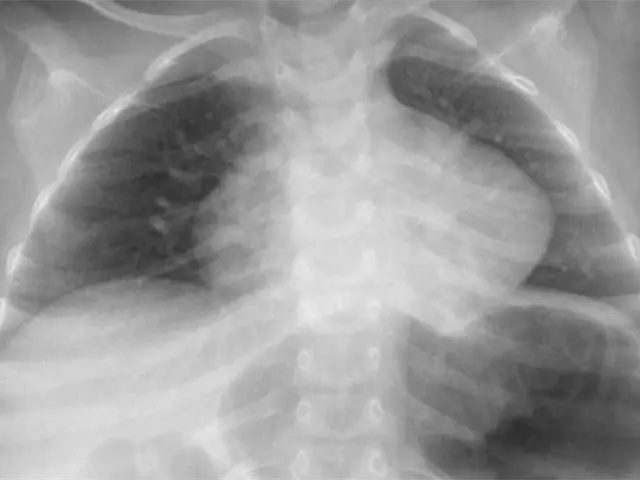

El pequeño Dylan, de apenas 2 años de edad, está delicado, ya que sufrió quemaduras graves en su esófago e infección en un pulmón, debido a que se tragó una pila, esto ocurrió en Hermosillo, Sonora.

La pila reventó en el interior de su organismo y provocó quemaduras en su estómago e infección en un pulmón.

La madre de Dylan, explicó que en un principio que lo llevó al Hospital de Cananea porque el niño presentaba dificultad para respirar y ahí le notificaron que había ingerido una pila.

Posteriormente, fue trasladado al HIES donde a través de diferentes aparatos oxigenan su sangre para poder operarlo.